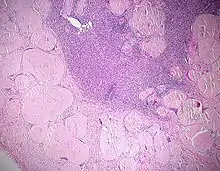

![]() Ausgeprägte Amyloidablagerungen (homogen rosa) in einem Lymphknoten, H&E. |

![]() Amyloidablagerungen in den Gefäßwänden, H&E. |